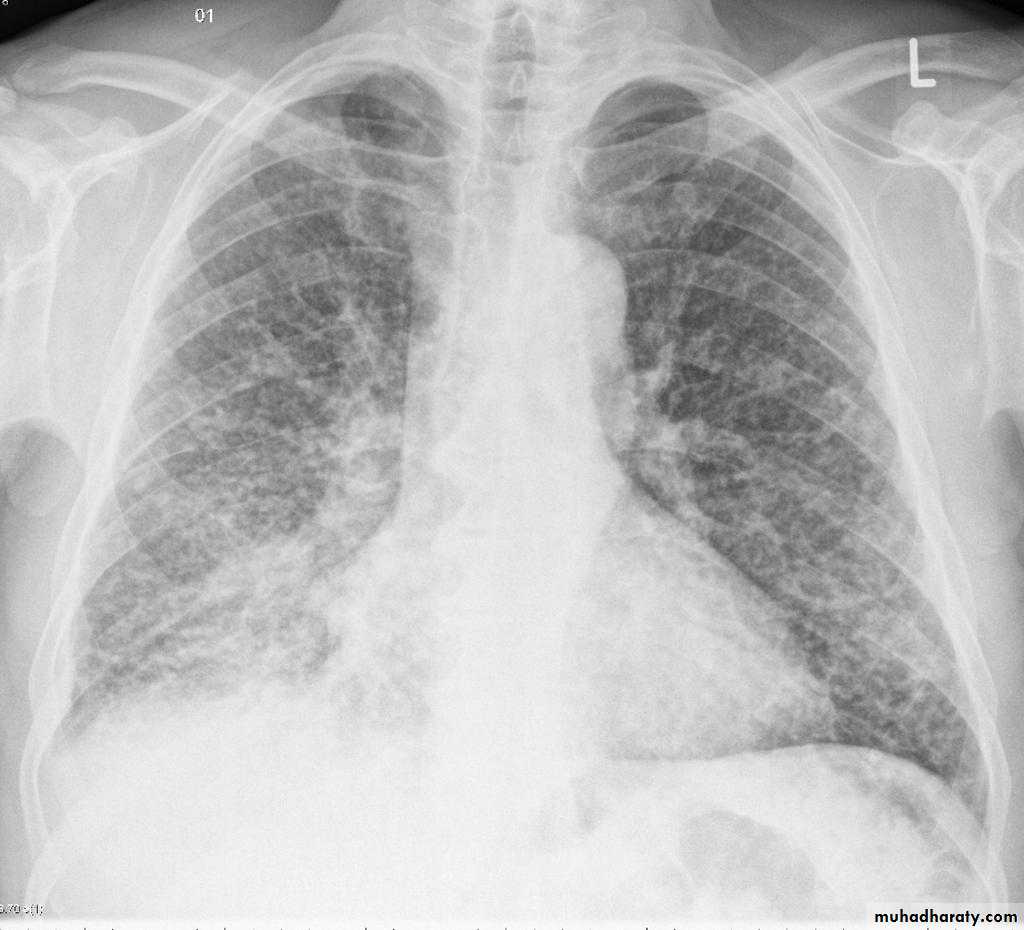

Miliary TB

65.Miliary TB

66.miliary TB